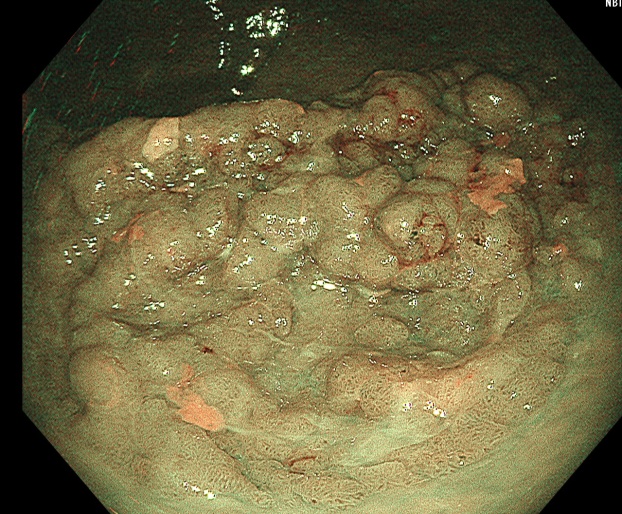

电子结肠镜能直观显示病变的部位、形态及大小(见图2),是临床常用的检查方法。LST,尤其是LST-NG,在常规白光内镜下难以有效检出,漏诊风险较高。因此,普通结肠镜检查中联合其他内镜检查方法不仅能显著提高LST的检出率,还可以借助其他内镜检查对病变的病理类型及浸润深度进行评估。常见的内镜下诊断技术包括放大内镜(magnify endoscopy, ME)联合染色内镜(staining endoscopy, SE)、内镜窄带成像(narrow band imaging, NBI)、蓝色激光成像(blue laser imaging, BLI)、超声内镜(endoscopic ultrasound, EUS)、计算机辅助检测(computer aided detection, CAD)等(见图3图4)。

Figure 2. LST lesion (WLI)

2. LST病变(白光)